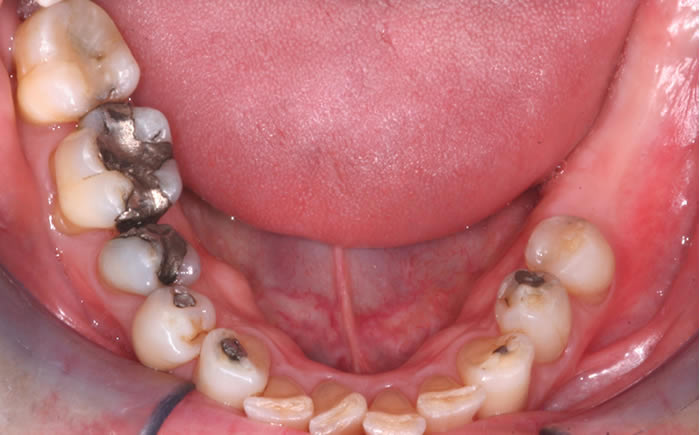

Gum disease

Case One (2 images)

Treatment of severe gum disease.